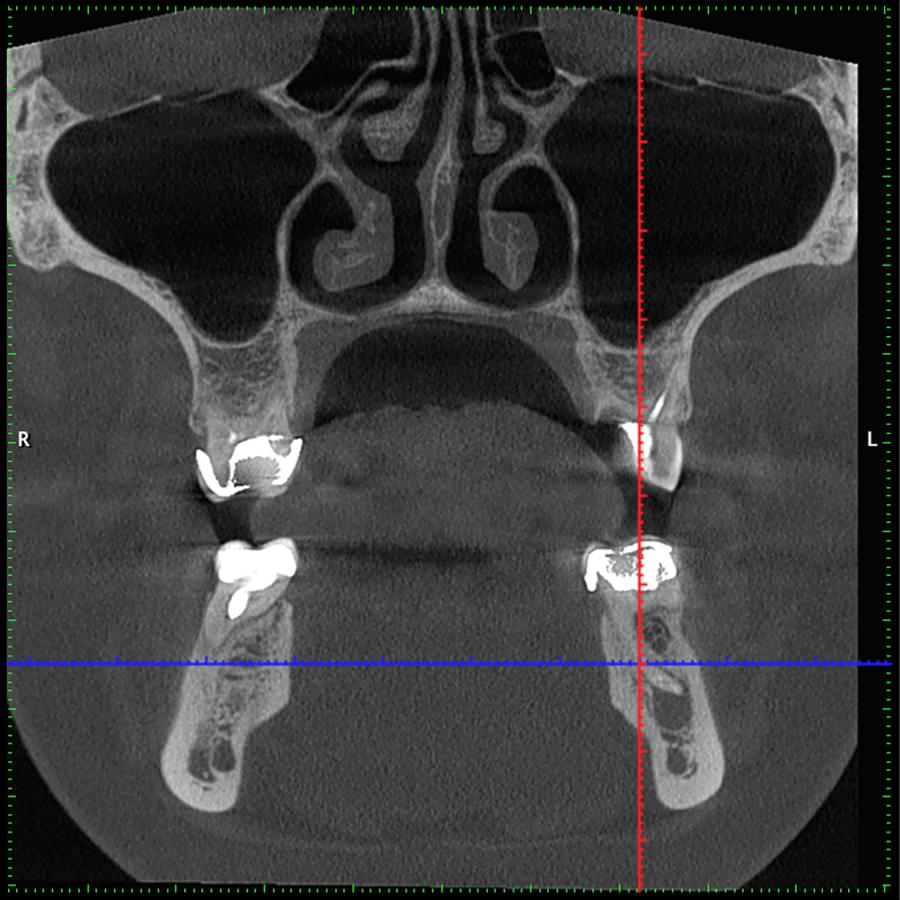

Комп'ютерна томографія

Щелепно-лицева діагностика

Мережа діагностичних центрів "МАЙРЕЙ ЛАБ" забезпечує точну та надійну діагностику

щелепно-лицевої ділянки з мінімальним ризиком для пацієнтів.

Ми використовуємо найсучасніше обладнання відомого виробника PLANMECA, що дозволяє отримувати високоякісні зображення за короткий час. Крім того, ми маємо власний сервер, на якому створюємо окрему скриньку для кожного лікаря, що забезпечує максимальну зручність та ефективність роботи.

3D цефалометричний аналіз є сучасною технологією, яка дозволяє отримувати точніші,

комплексніші та надійніші дані про зубну та скелетну структуру. Ця технологія може стати

великим кроком в перед для ортодонтів, які хочуть забезпечити найкраще можливе лікування

своїх пацієнтів.

Основні переваги 3D цефалометричного аналізу:

Точність: 3D цефалометричний аналіз забезпечує точніше визначення розмірів та відстаней між

зубами та кістковими структурами.

Комплексність: ця технологія дозволяє отримувати детальні дані про різні структури, такі як

кістка та м'язи, що дозволяє ортодонтам докладніше досліджувати деякі патології та планувати

лікування.

Надійність: 3D цефалометричний аналіз дозволяє отримувати надійніші результати, оскільки

виключає можливість помилок, пов'язаних зі спотворенням або перекриттям зображень.